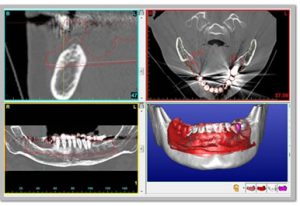

当院が導入しております最新の歯科用CT「SL」を使用することで、どの角度からでも口腔内の歯、骨格、神経など歯科治療に必要な情報を確認することが出来ます。また、従来のCTではデータ解析をするのに多大な時間を要し、診断可能になるまで14日以上ものロスがありましたが、このCTは撮影して数分後に口腔内を確認することが可能となっております。

インプラント治療計画ソフトウェア 複雑な治療計画をサポート

CGのインプラントソフトウェアは、神経管や骨格がビジュアル化され確認しやすく解剖学的な私見を必要とする患者様のインプラント治療に適したソフトウェアです。より正確なプランニングと埋入により安全性の確保を促し、不要なストレスが低減されます。治療状態を確認しインプラント埋入本数を増やすだけではなく、患者様へのプレゼンテーションにおいても3D画像により患者様への説明をサポートします。

CTを使用しての設計